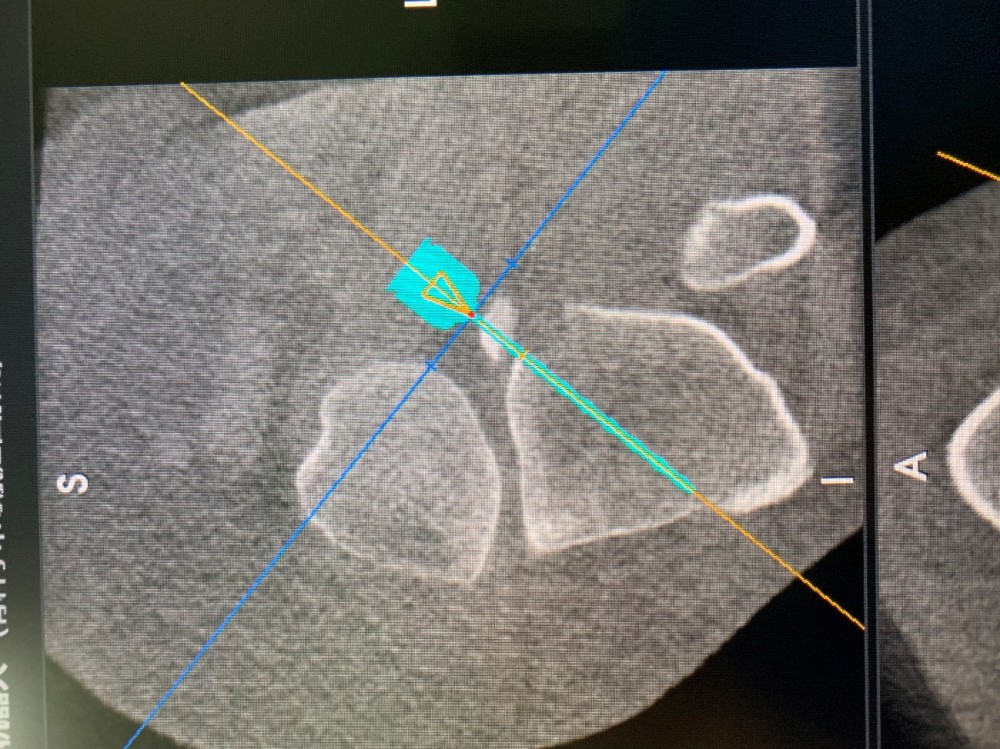

患者因外伤导致左胫骨髁间棘骨折,骨折移位明显,具备手术指征。但患者为年轻女性,担心手术瘢痕影响美观,传统手术方式无法满足患者需求。综合考虑后,91直播 创伤外科中心王建忠教授团队为患者制定了应用骨科手术机器人辅助下进行微创手术的诊疗方案。通过机器人进行数据采集、手术规划等人工智能手段,术中仅用约2cm切口即成功完成手术。与传统手术相比,此类手术切口明显减小,出血量少,达到了微创、精准的手术效果,患者及家属非常满意。

术前机器人设计手术入路